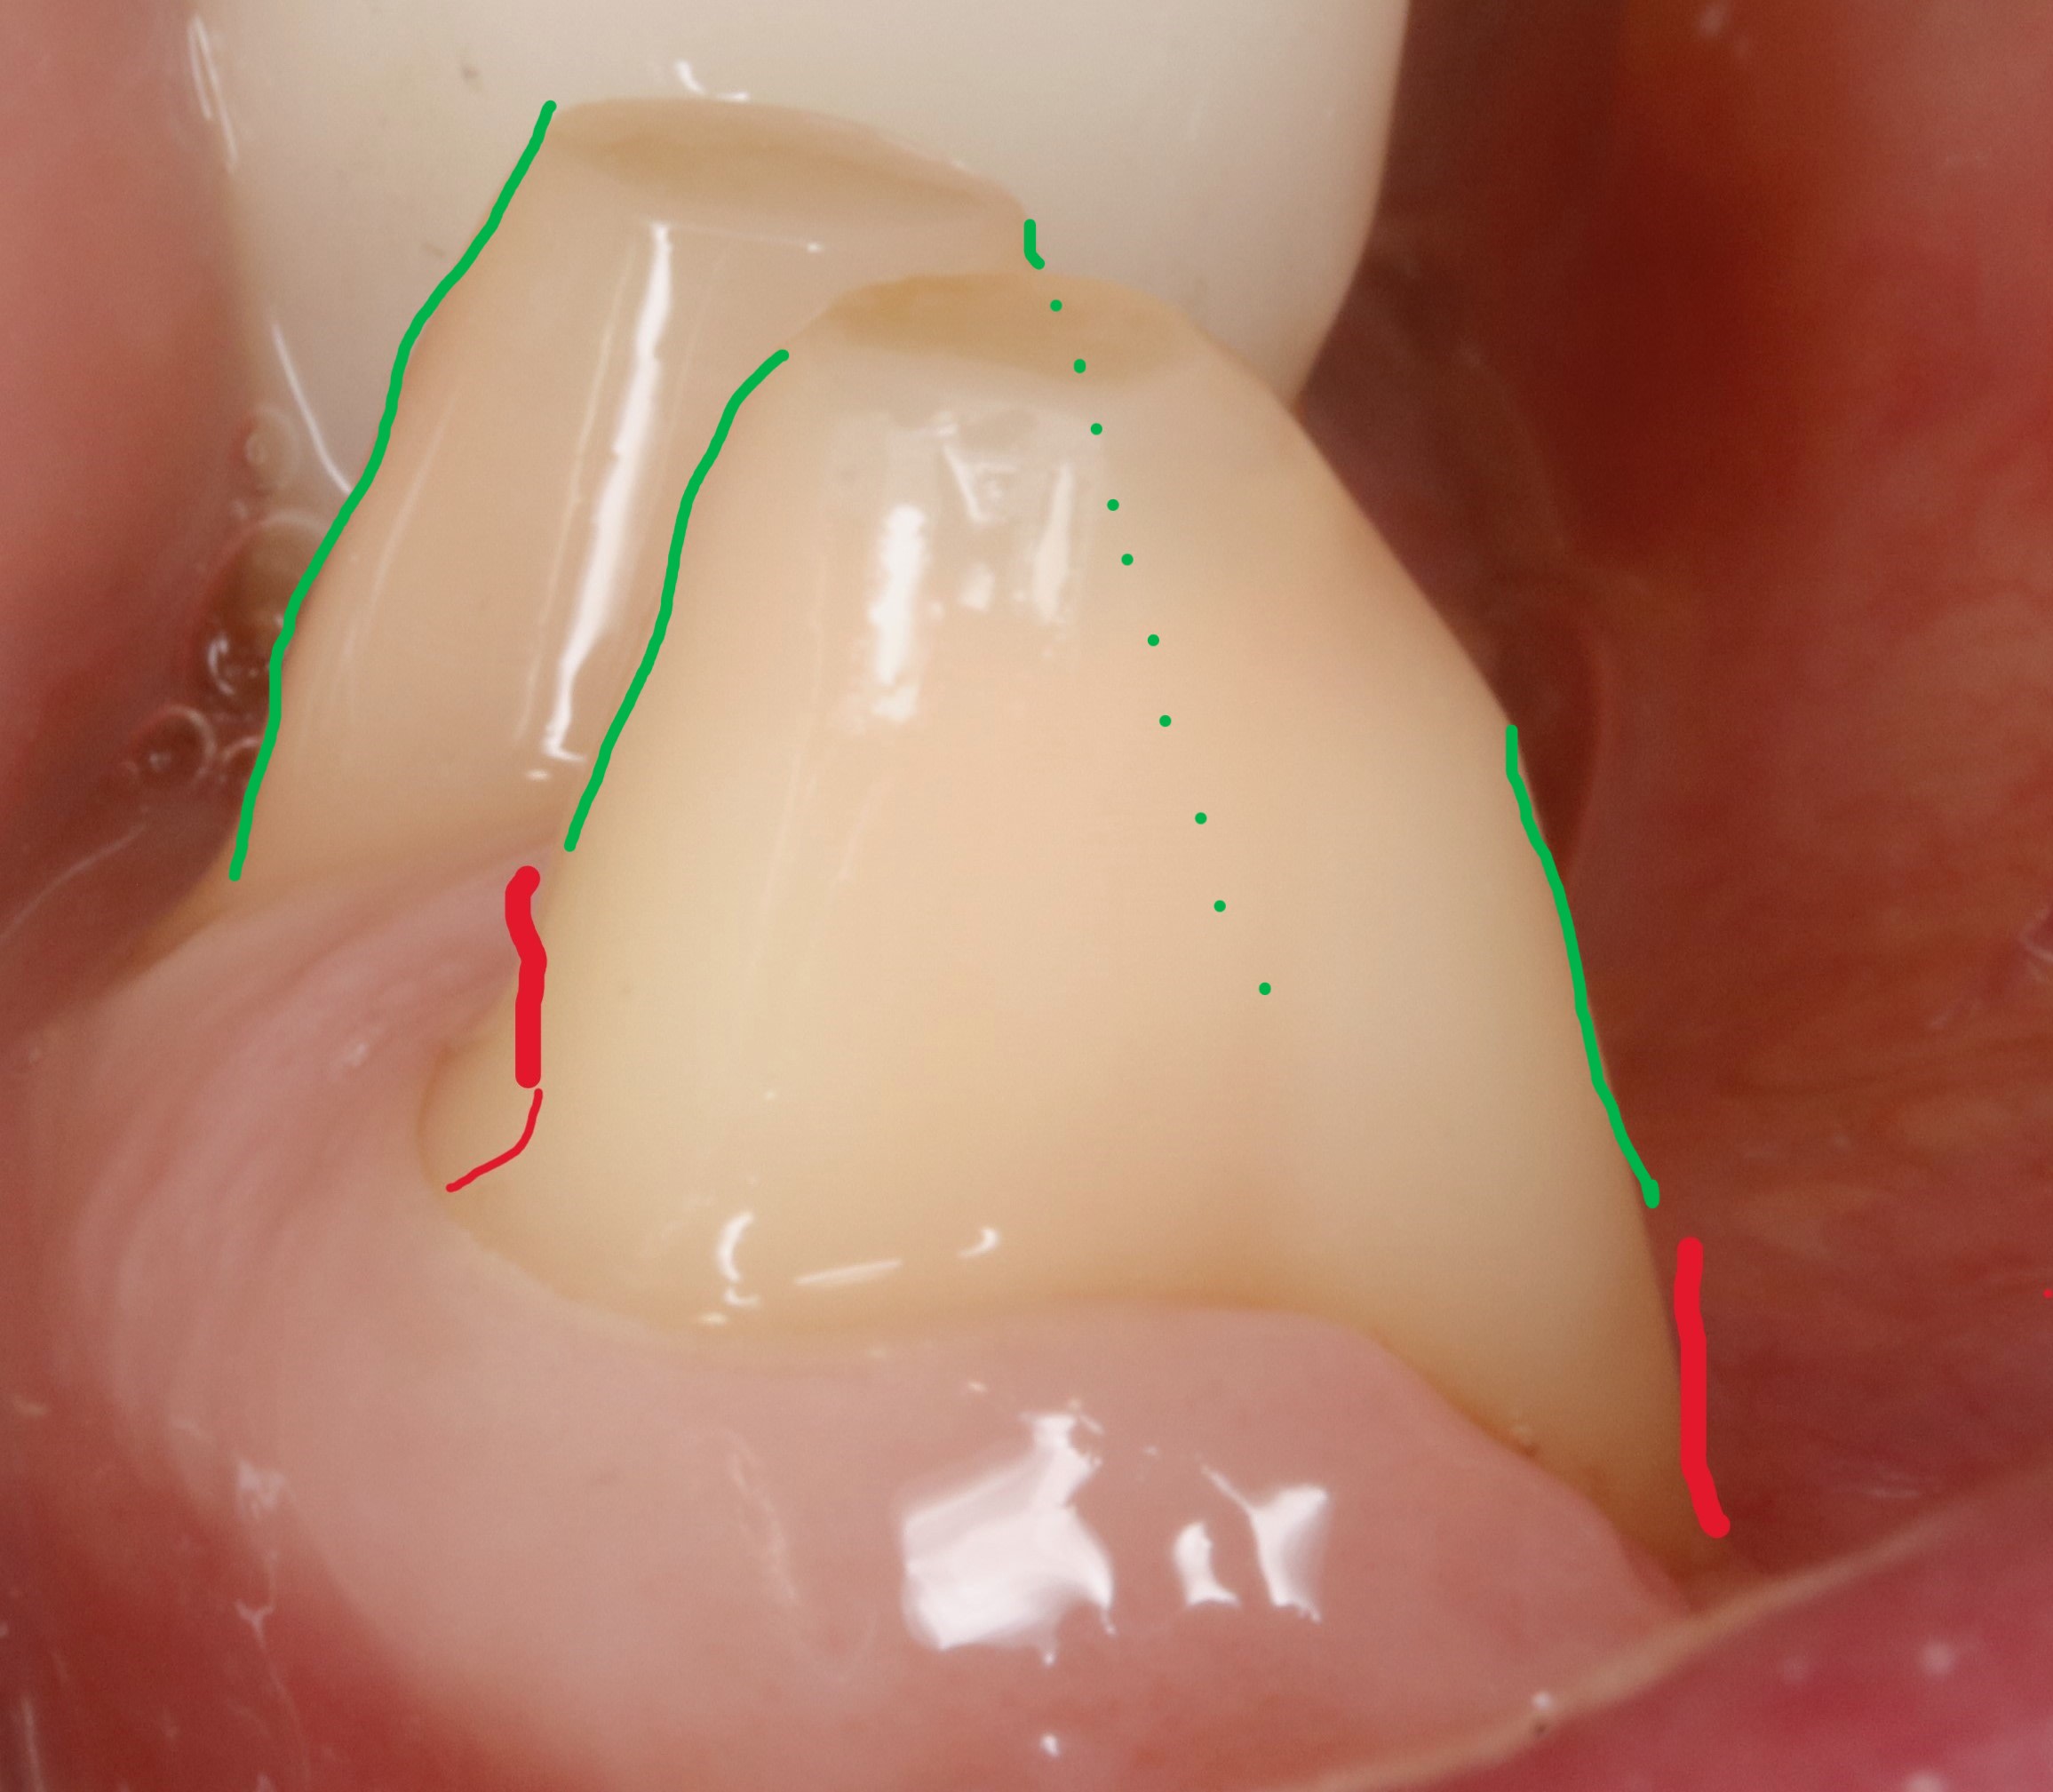

Daryl on va parler de la conicité , et tu vas voir qu ici par exemple eh bien ce n est pas si conique que ça , c est d'ailleurs pour ça que le prov tient tout seul.

la conicité vient toute seule , ce n est pas toi qui la détermine , c est la fraise et le cas prothétique .

la conicité tu la subis et faut jouer avec .

ici , on doit faire un bridge canine canine .les autres dents sont juste des piliers accessoires .

dejà , le bridge canine +accessoires par sa forme de fer à cheval est auto stable puisque les forces principales viennent d en haut et de devant .

les canines etant les plus costaudes , on va donc essayer de ne pas trop les fracasser et les choisir comme axe d insertion . ce sera donc notre axe de taille directeur . cet axe etant bien sur l axe moyen (ou commun) entre les deux .

donc on commence par tailler les canines en mettant de dépouille .

devant ( en vestibulaire ) on a vu que c etait auto stable , à condition bien sur de laisser la place au montage des dents . donc la courbure de devant dépend de la forme cingulaire des dents du haut .eh oui :-)

là on a pas encore parlé de congés ou quoi que ce soit .

alors maintenant derrière c est diffèrent , avec la langue , ce n est pas du tout auto stable , et vu que devant c est assez incliné , il va falloir trouver de la rétention . et y en a pas beaucoup et elle se trouve juste au depart de la dent . elle est si précieuse qu une fois taillée , on y reviendra plus jamais .

ce sera notre axe de rétention de référence pour tout le bridge .

et on ne peut pas dire qu il y ait de la conicité entre les deux .

voir les traits bleus sur la photo , sauf si comme dans mission impossible , elle disparait .:-)

arrive maintenant le congé .

on a vu qu en vest , du fait que ce soit penché à cause des dents du haut , ce serait bien de rajouter une opposition avec la face linguale .

donc au pied si on pouvait rentrer un peu tout en redressant ce serait pas mal .

ben voilà , il sert à ca le congé , le voilà . à faire la férule de PP :-)

en plus ca fait plaisir au labo qui va pouvoir s amuser dessus à faire l artiste .

le congé doit donc servir à réduire la conicité .

c est pour ca qu il doit être fait APRES la face linguale .

puisque que peuchère , la face linguale étant limitée , on s adapte à elle et on parallélise à mort , enfin on essaye .

traits rouges sur photos .